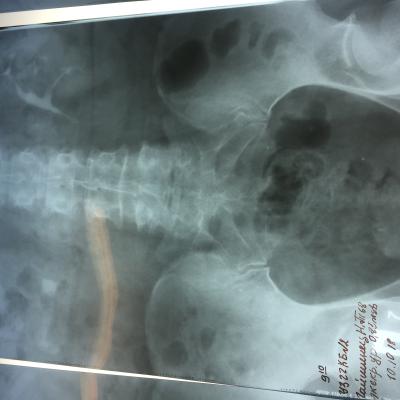

Камень в почках размер 25 мм

Беспокоила тяжесть в почке и периодические боли, часто выходили мелкие камни, после очередного приступа обратилась к врачу и попала в Больницу, сделали снимки ( фото прилагается) обнаружен крупный камень размером 25 мм и несколько мелких . Что делать? Не знаю? Дайте пожалуйста рекомендации!!! Удалять камень? Каким способом операция либо новыми технологиями это возможно?